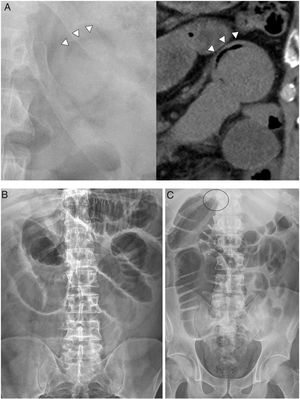

Although plain radiography is usually the first examination, the specific intussusception findings described in the literature, such as the "crescent sign'' (gas between the intussusceptum and the intussuscipiens)16, are rare in practice. In fact, we only identified it in one of our patients (Fig. 1A). However, the radiograph may reveal complications such as pneumoperitoneum or signs of obstruction, sometimes indicating the location of the change in calibre (Fig. 1B and C).

Plain radiography. A) "Crescent sign'': radiolucent crescent of gas trapped between the wall of a loop and the intussusceptum. B) Obstruction of the small intestine: distension of the loops of the small intestine with the absence of gas in the colon. C) Obstruction of the colon: dilation of the ascending colon to the proximal transverse colon, possible location of the obstruction (circle).